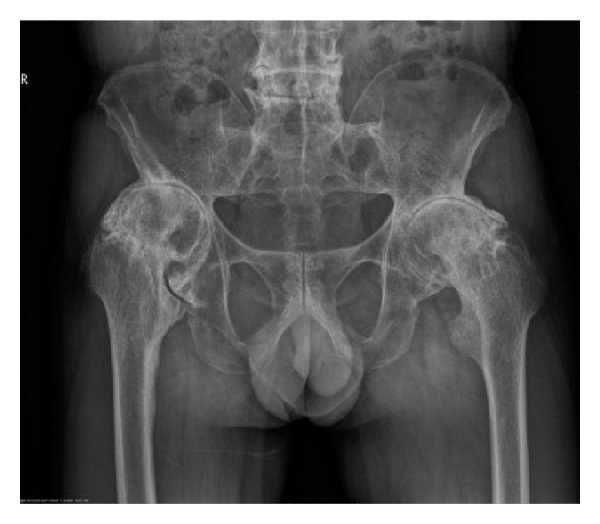

Preoperative characteristics of patients are listed in Table 1. The mean age and disease duration of patients were 37.1 ± 9.0 years (range: 24–52 years) and 13.7 ± 12.4 years (range: 2–40 years), respectively. HLA-B27 was positive in all patients. RF and ANA were negative. No patient had a history of iritis. Five patients had elevated ESR (5/7, 71.4%). Six patients had increased CRP (6/7, 85.7%). Radiographic evaluation of hips showed narrowed joint spaces ranging from 0 to 7 mm, including 3 of 7 patients with complete disappearance of the joint space (Figure 1). Serum levels of IgG and IgG4 were not measured.

(a)

(b)

(c)

(d)